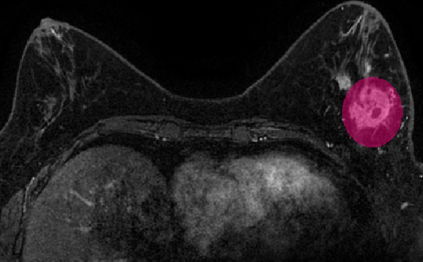

Most papers caution against using predictive models for disease stratification based on unselected radiomic features, as these features are affected by contouring variability. Instead, they advocate for the use of the Intraclass Correlation Coefficient (ICC) as a measure of stability for feature selection. However, the direct effect of segmentation variability on the predictive models is rarely studied. This study investigates the impact of segmentation variability on feature stability and predictive performance in radiomics-based prediction of Triple-Negative Breast Cancer (TNBC) subtype using Magnetic Resonance Imaging. A total of 244 images from the Duke dataset were used, with segmentation variability introduced through modifications of manual segmentations. For each mask, explainable radiomic features were selected using the Shapley Additive exPlanations method and used to train logistic regression models. Feature stability across segmentations was assessed via ICC, Pearson's correlation, and reliability scores quantifying the relationship between feature stability and segmentation variability. Results indicate that segmentation accuracy does not significantly impact predictive performance. While incorporating peritumoral information may reduce feature reproducibility, it does not diminish feature predictive capability. Moreover, feature selection in predictive models is not inherently tied to feature stability with respect to segmentation, suggesting that an overreliance on ICC or reliability scores for feature selection might exclude valuable predictive features.